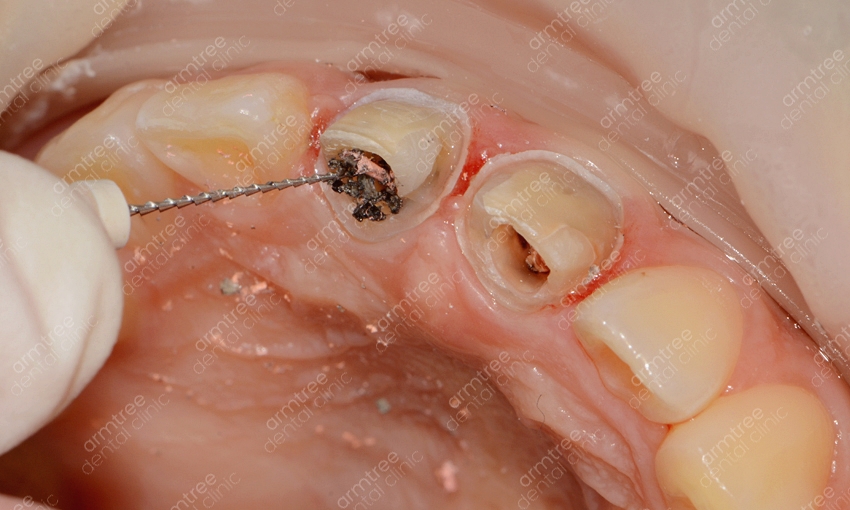

실활치란 용어는 외상이나 충치 등으로 인하여 치아 속 치수가 죽는 증상을 의미해요. 그로 인해 혈액과 신경 활동이 원활하게 이루어지지 않아 치아가 약해지고 어둡게 변하기도 하는 것이에요. 이러한 치아 내부의 출혈 색소나 염증 부산물을 제거하는 신경치료를 선 진행한 후 치아 내부에 미백제를 넣어 다시 치아색을 밝게 한 후 레진으로 막는 치료법이에요. 일반적인 생활치미백에 비해 진행과정이 까다로운 편이기 때문에 관련하여 장비를 갖추고 있고 해당 경험이 풍부한 곳에서 치료를 받는 것이 좋았어요. 신논현역치과 아름드리치과에 사용되는 약재에 대해 신체에 해로울까 걱정하시는 분들도 계시는데요. 사용되는 약재는 치아 속에 과산화수소수 계열의 약재를 넣어놓고 환자가 생활하시는 동안에 미백이 진행되게 하는 것이라 영어로는 Walking blwaching라고도 불리는데요. 실제로 진행 시 치아 하부 구조 사이에 수복재료를 쌓고 진행하는 것이라 전문 의료진과 함께 한다면 크게 위험하지 않은 시술이라고 할 수 있었어요. 하지만 이 역시 정확하게 수복재료를 적용하지 않고 무분별한 진행을 한다면 치아 외 흡수가 발생할 수 있으므로 받드시 경험이 많은 의료진의 시술이 필요한 과정이었어요.

실활치미백은 치아가 전체적으로 변색되어 하는 일반적인 치아미백과는 다른 것이 특정치아 특히 앞니만 변색되거나 1-2개의 치아의 색이 변한 경우 진행하는 경우가 많은데요. 치아 1-2개의 색만 검게 변한다면 전체적으로 누렇거나 하얗지 못하게 되었을 때 보다 더 어색하거나 튀어서 도드라지게 보일 수 있기에 적절한 치료를 통해 주변 치아의 색과 유사하도록 해주는 것이 효과적이에요. 또 일반적인 치아미백이라면 미백제의 농도 조절이나 미백 광선의 조사방법이 중요한데 실활치미백은 먼저 신경치료가 선행되어야 하기에 보다 정교한 시술이 필요해요. 신경조직은 여러 갈래로 나뉘어져 섬세한 치료를 요하는 시술이기 때문인데요. 신논현역치과 아름드리치과에서는 3D 첨단 장비를 구비하고 있어 세세한 부분까지 신경치료를 진행할 수 있을 뿐 아니라 항시 임상경험이 풍부한 의료진이 대기하고 있어 정확하고 안전한 시술을 기대할 수 있었어요. 또 신논현역치과에서는 환자 개인마다 다른 환자의 구강환경에 맞춰 1:1 맞춤 플랜을 세워 치료를 진행하고 있었어요. 아름드리치과는 앞니 단일 치아의 변색일 때에는 외상으로 인한 치아 신경의 염증, 치아의 신경인 치수 잔사 등 미세한 염증이 존재하는 경우, 기존 신경치료 후 레진 수복 후 레진 수복재료사이의 미세누출로 염증이 생긴 경우 등 다양한 경우의 원인이 있을 수 있어요. 그렇기에 보다 정확한 진단 검사와 그에 따른 치료계획을 수립하는 것이 중요한 과정이라 볼 수 있었어요. 미백치료의 경우 집에서 셀프로도 많이들 진행하시지만 미백 후에 효과가 별로 없다거나 1-2의 치아만 유독 변색이 심하다면 집에서 직접 하는 방식으로는 치료가 불가능하기에 꼭 신논현역치과 아름드리치과를 내원하시길 권해드리겠어요.